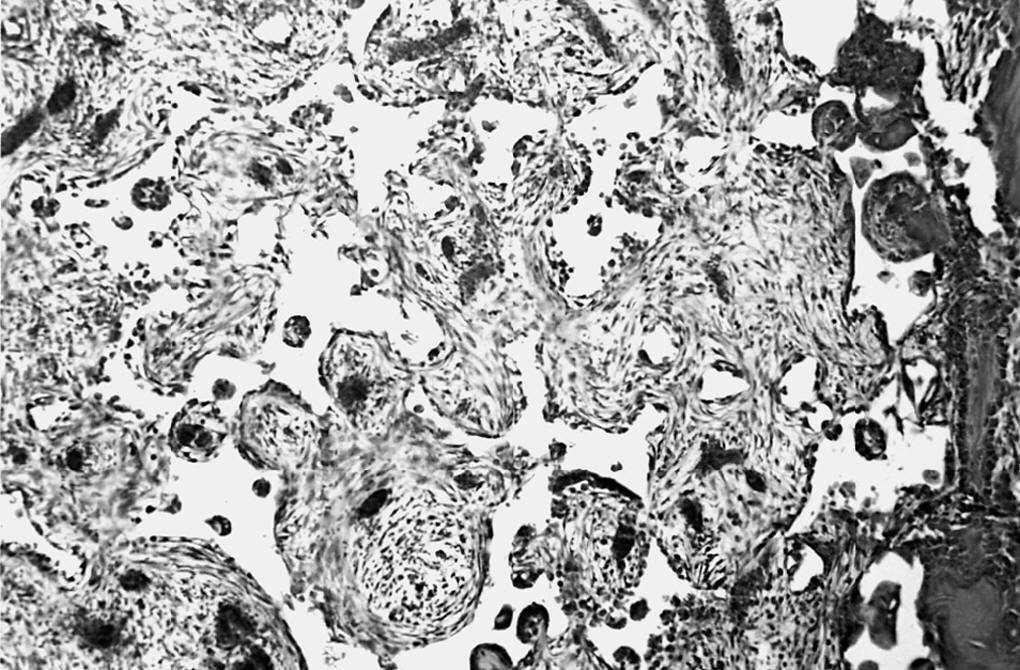

Los poros del implante se observaron parcialmente ocupados por tejido de granulación joven, constituido por numerosas yemas endoteliales y vasos sanguíneos de calibre capilar, así como abundantes células mesenquimales de morfología irregular de citoplasmas amplios, y numerosos fibroblastos dispuestos al azar en el seno de abundante sustancia fundamental. Las fibras colágenas se disponían de forma irregular y frecuentes macrófagos y linfocitos dispersos (fig. 2).

Figura 2. Tejido de granulación que ocupa los poros de la espuma (*) y trabéculas óseas (↑) (zona derecha) (HE, 312,5 x).

En el seno del tejido de granulación, en contacto con la cortical, así como en la periferia del material implantado, se observó escaso material osteoide, así como trabéculas óseas neoformadas, que eran más abundantes en las zonas adyacentes a la cortical. Los fenómenos de regeneración ósea afectaron entre el 10 y 15% del cilindro implantado y estaban constituidos por trabéculas óseas neoformadas, que delimitaban parcialmente al cilindro.

Las imágenes de MEB concuerdan con las de microscopia óptica, destacando en la cortical la costra fibrino-hemática. Por debajo de la cortical y rodeando al implante observamos tejido de granulación formado por fibras y abundante celularidad que ocupaba parcialmente los poros (fig. 3).